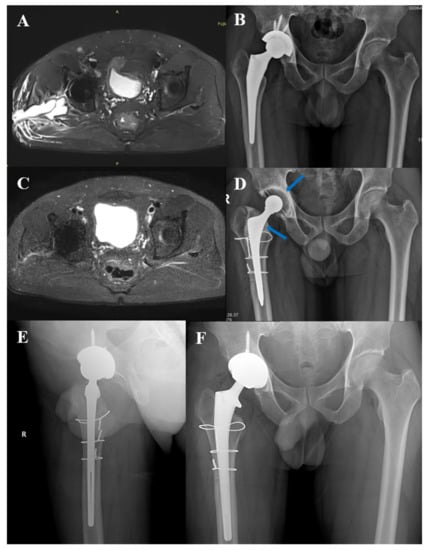

3.5. Typical Cases